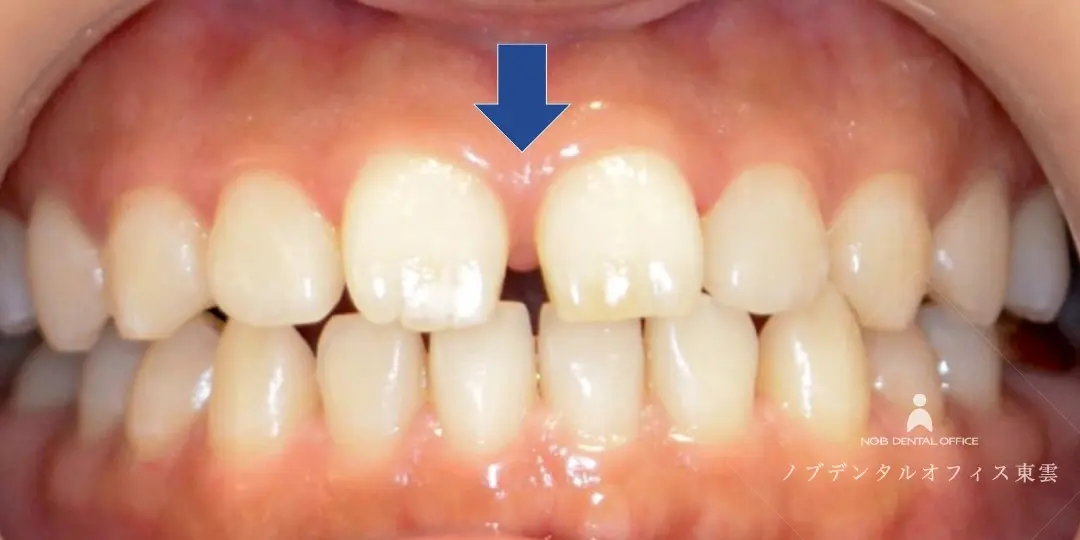

すきっ歯をコンポジットレジンで治した症例(20代女性)

「前歯のすき間が気になる」「笑った時の見た目をきれいにしたい」とご来院されました。

コンポジットレジンで修復することで、1日で治療が完了しました。

前歯の形態とバランスを整えました。

| 費用 | コンポジットレジン 55,000円(税込) 保険適応外 |

| リスク | ・経年的に摩耗が起こることがあります。 ・噛みしめや歯ぎしりにより、欠けたり外れる可能性があります。 ・清掃状態や生活習慣によ っては境目から虫歯や歯周病が起こることがあります。 |